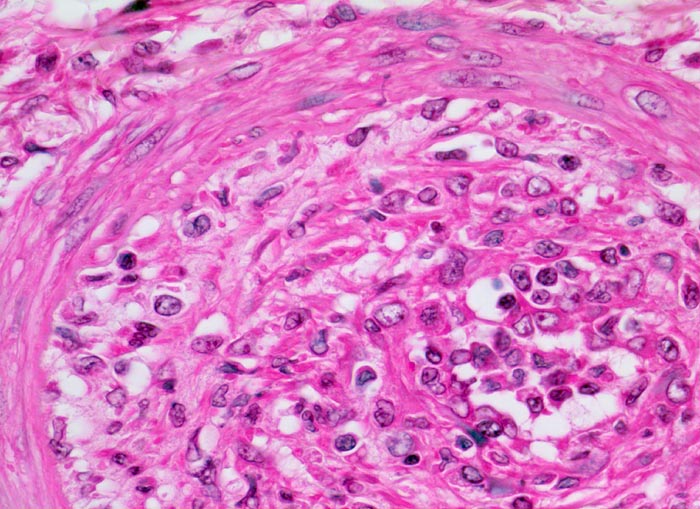

• Akute Abstossung (vorliegendes Präparat):

Typischerweise innert 1 bis 5 Wochen (meist innerhalb der ersten 3 Monate, kann aber jederzeit auftreten) nach Transplantation. Es handelt sich in erster Linie um einen zellvermittelten Prozess mit antigenspezifischer Immunantwort bei Histoinkompatibilität zwischen Spender und Empfänger (Coombs-Typ IV). Bei einem Grossteil der akuten Abstossungen mit Gefässbefall (Endarteritis) und/oder Transplantat-Glomerulitis sind gleichzeitig Antikörper gegen HLA-Antigene nachweisbar. Bei den meisten akuten Abstossungsreaktionen besteht ausschliesslich eine tubulo-interstitielle Entzündung mit Lymphozyten, Histiozyten und später Plasmazellen. Der Prozess ist heute meist reversibel. Histologisch unterscheidet man eine akute tubulointerstitielle, eine vaskuläre, selten eine glomeruläre Abstossung und Mischformen.

Morphologische Merkmale:

• Eine von 6 grossen bzw. mittelgrossen Interlobulararterien mit segmental verbreiterter, fibrosierter Intima mit Myofibroblasten und mit subendothelial gelegenen Leukozyten (Endothelialitis)